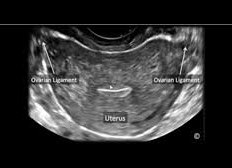

Gynecological Ultrasound

Rule out Fibroids, Ovarian Cysts and numerous gynecological pathologies

Transabdominal evaluation of complete gynecological anatomy, including uterus, cervix, ovaries/adnexa, and urinary bladder.